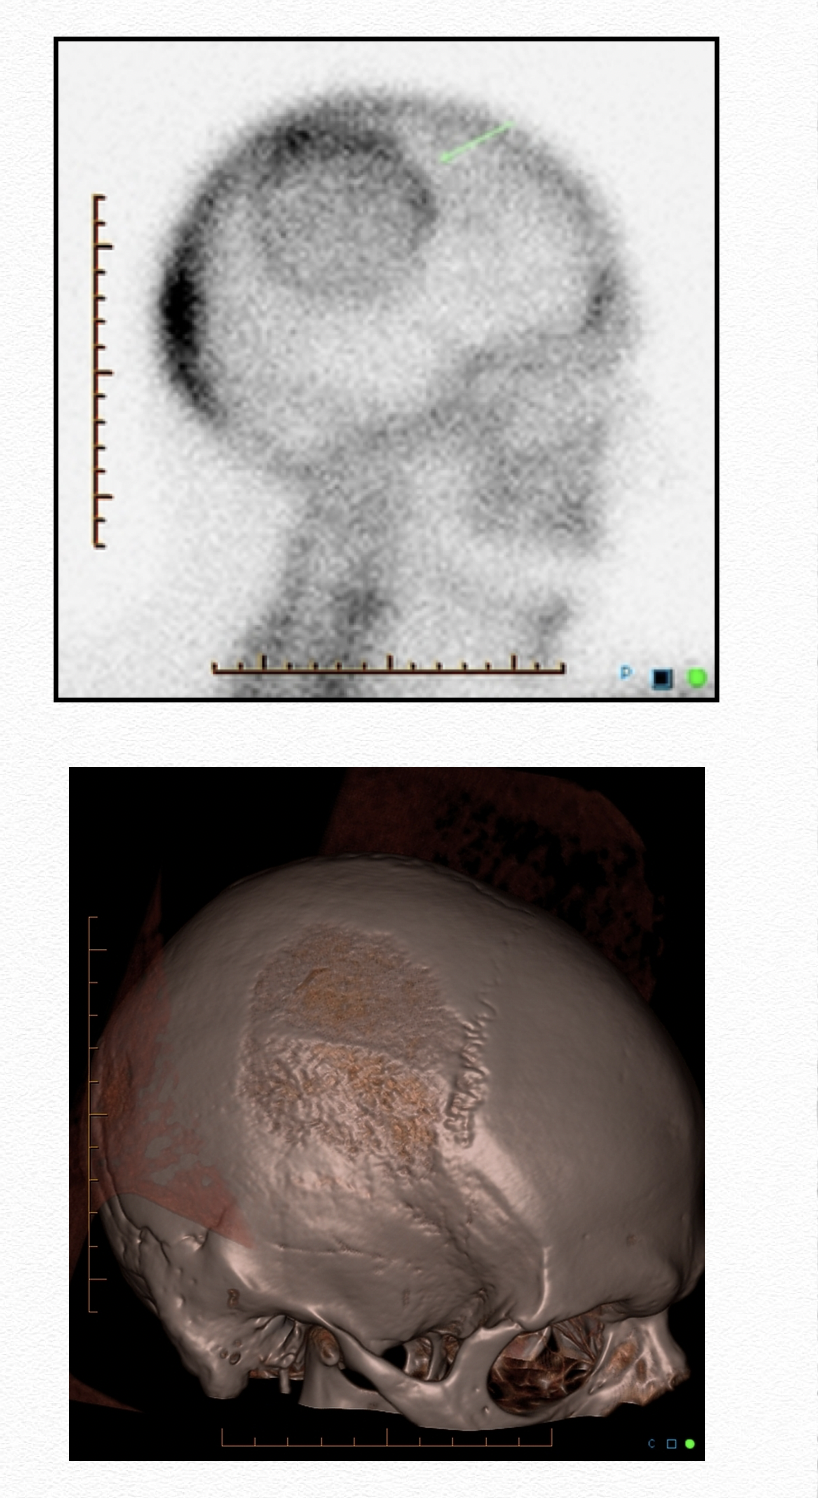

Mickey Mouse sign

Image

• Characteristic appearance of vertebral Paget’s disease

• Abnormal tracer accumulation throughout the vertebra

• Affecting body and posterior elements

• Clover/heart/Mickey Mouse sign